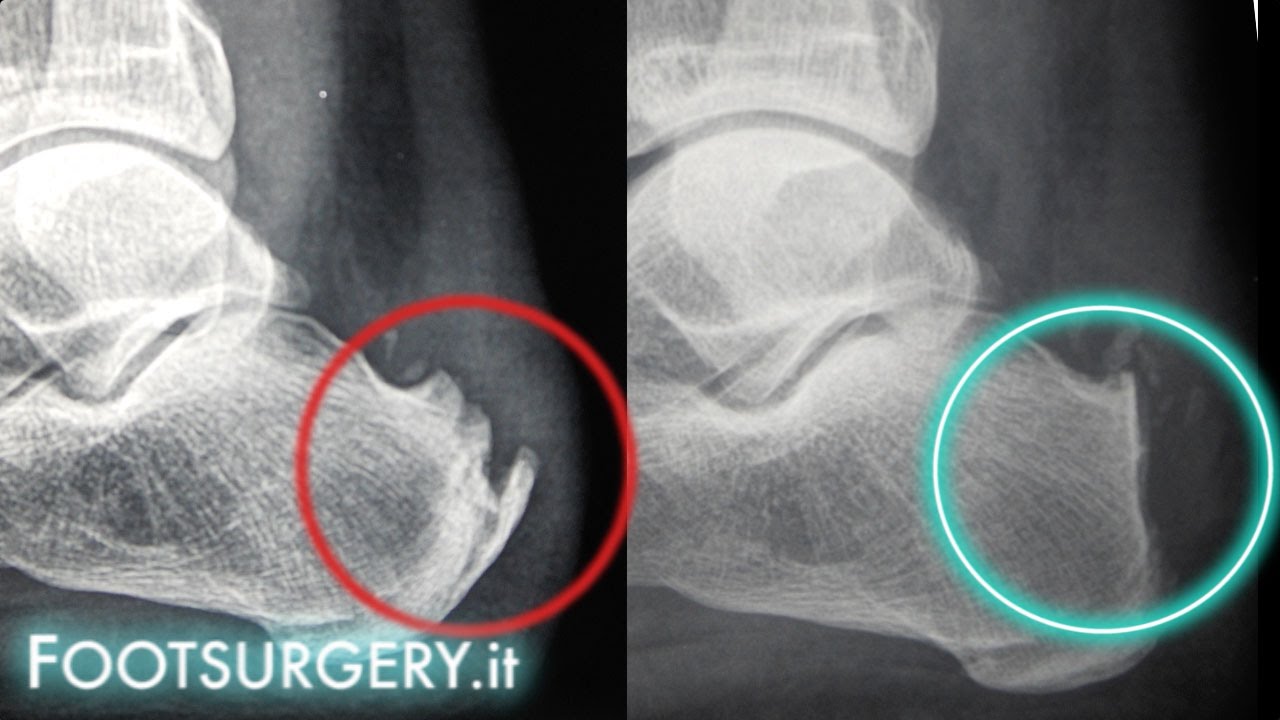

WebCurare la Malattia di Haglund ovvero la sporgenza ossea del calcagno. Il filmato mostra un paziente operato un mese prima di malattia di Haglund a livello del calcagno sinistro. Il paziente indossa le scarpe da ginnastica. Prima dell’intervento ciò. WebLa riabilitazione post-intervento è uno dei vari problemi postoperatori dello sportivo che si è sottoposto a un intervento chirurgico. Sfortunatamente è praticamente impossibile trovare un riabilitatore che sappia definire esattamente il cammino postoperatorio. WebNel post operatorio si consiglia al paziente di sollevare la gamba per 5-7 giorni dopo l’intervento con l’utilizzo di immobilizzazione bendata compressiva e l’applicazione regolare di ghiaccio e farmaci antinfiammatori non steroidei per ridurre gonfiore e infiammazione. WebTrattare chirurgicamente il paziente per morbo di Haglund regolarizzando l’esostosi calcaneare quando i disturbi sono dovuti alla tendinopatia calcifica dell’Achilleo e’ un errore assolutamente da evitare ma al quale purtroppo capita ancora spesso di assistere. WebL’intervento chirurgico e la riabilitazione post-operatoria. La sindrome, malattia o morbo, di Haglund è una patologia che colpisce il calcagno per lo più delle persone giovani e sportive. Questa malattia genera una sorta di tallone sporgente che, infiammando il. WebQuali sono le cause del morbo di Haglund? Il morbo di Haglund si verifica quando si applica una pressione frequente sul tallone . Può essere causato dall’indossare scarpe troppo strette o rigide. WebMalattia di Haglund: quando e come va operata. La malattia di Haglund è una patologia del retropiede caratterizzata dalla presenza di una prominenza eccessiva dell’angolo postero-superiore del calcagno (Fig.1) con il conseguente attrito con il tendine d’Achille e la borsa.

Malattia di haglund